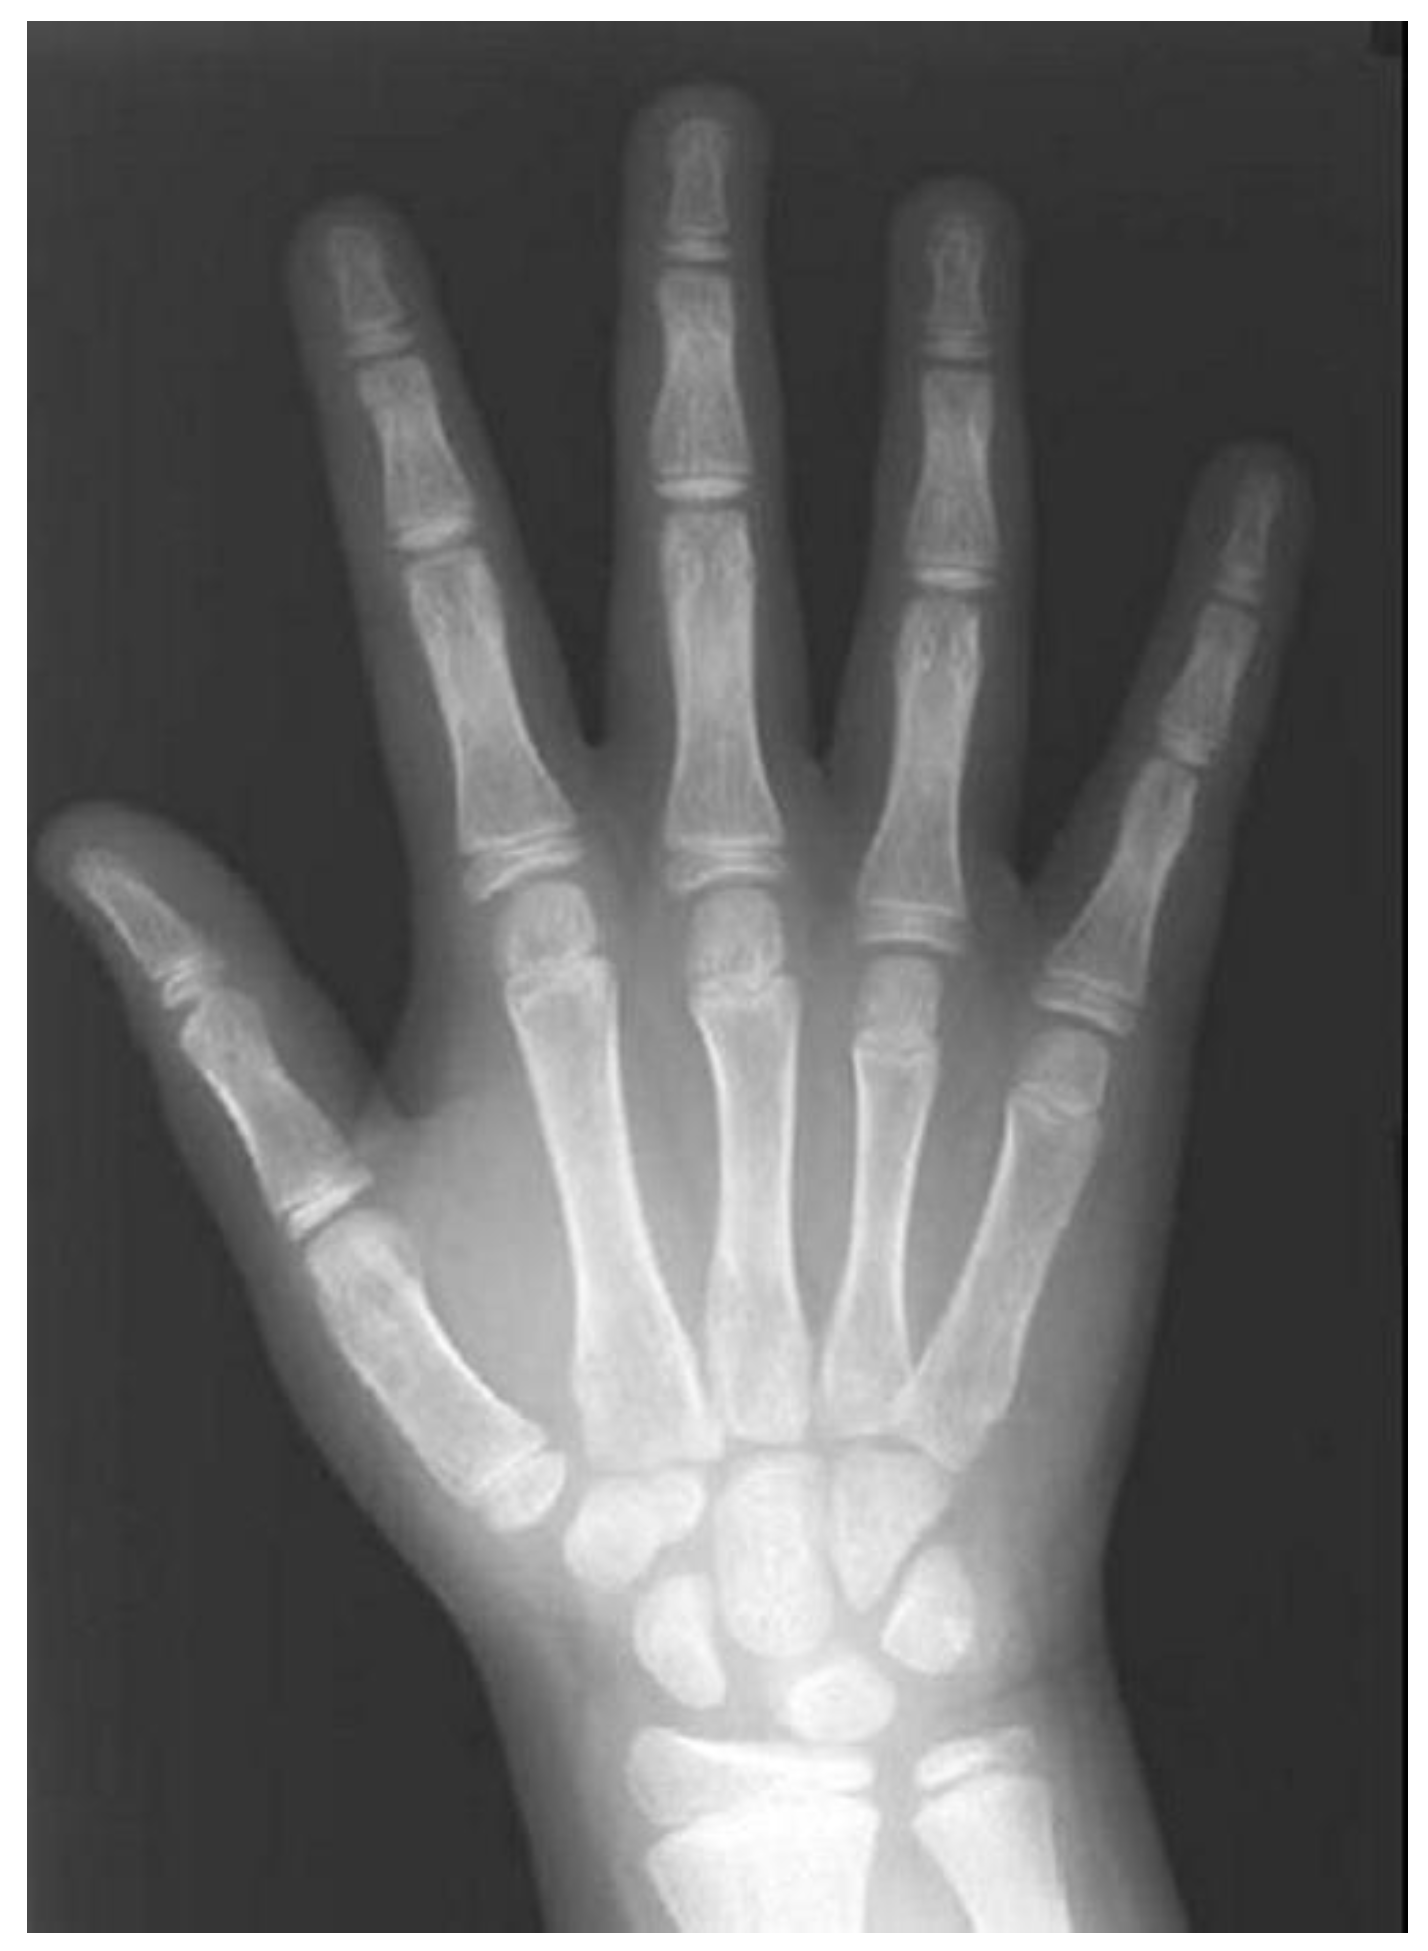

- Skeletal age is commonly assessed using cervical vertebrae and hand–wrist radiographs. Alternative approaches, including metal implants, biochemical markers, and electromyography, have been implemented.

3.3.3. Hand–Wrist Radiograph

| HWR | hand–wrist radiograph |